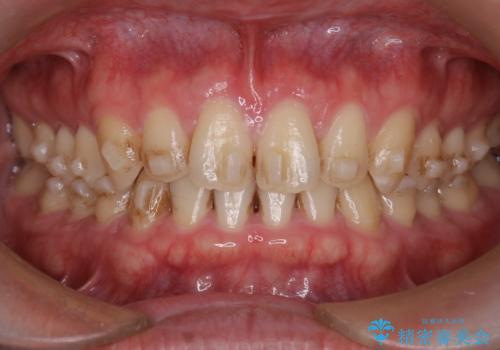

【インビザライン】前歯の隙間を治したい。

- 前歯の隙間を主訴に来院されました。

インビザラインにて治療しました。

ディープバイトも改善でき患者さんも満足されていました。

前歯の隙間だけを閉じる治療を行うだけでは、噛み合わせが悪くなるためディープバイトも改善が必要です。